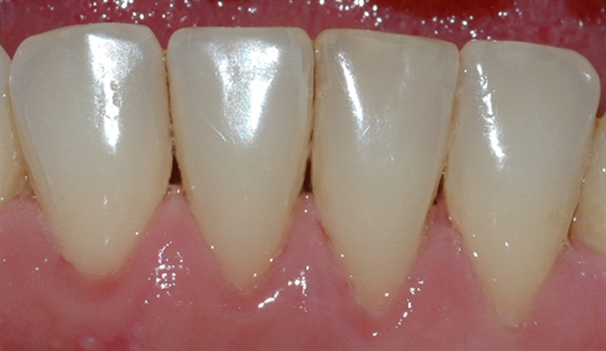

perio stor 1

Bildet viser tilsynelatende normale tannkjøttsforhold ved tenner i underkjeven.